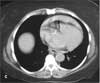

CT scan without contrast. A CT image through the ascending aorta is obtained without intravenous contrast (B). This reveals a linear area of fluid within the ascending aorta (B, arrow). The fluid represents blood in the displaced intimal wall of the ascending aorta, which is diagnostic of aortic dissection. Another noncontrast image, slightly inferior to the first, shows high-density fluid, consistent with blood, in the anterior pericardial sac (C, arrow).